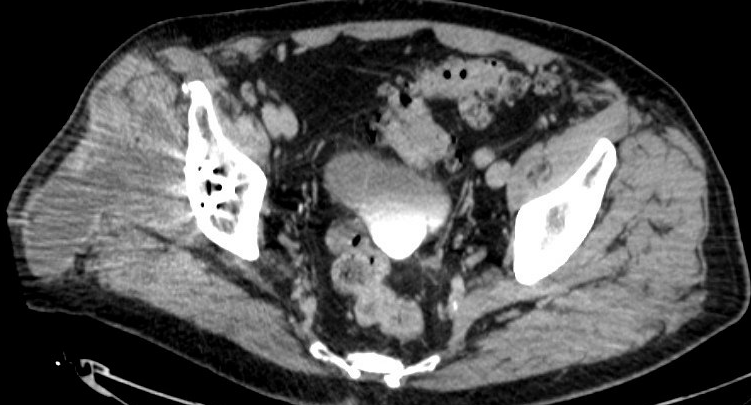

MRI / CT

CT demonstrating large fluid collection around THA